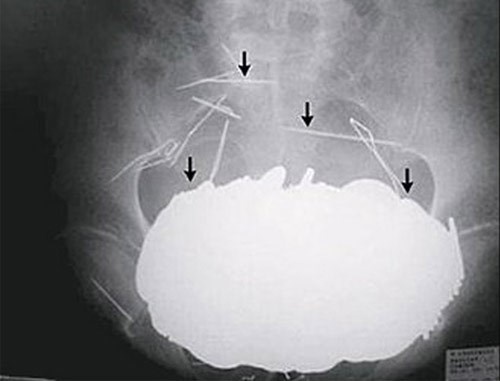

| Cô Nicole Haynes đã qua đời bất ngờ sau ca phẫu thuật nội soi ổ bụng đơn giản. Sau đó nhân viên bệnh viện đã phát hiện một đoạn phim ghi lại toàn bộ quá trình phẫu thuật. Nội dung đoạn phim cho thấy, các bác sĩ chịu trách nhiệm về ca mổ đã bỏ quên… kéo trong bụng bệnh nhân và không thực hiện đầy đủ những thao tác cần thiết khi hoàn thành phẫu thuật. |